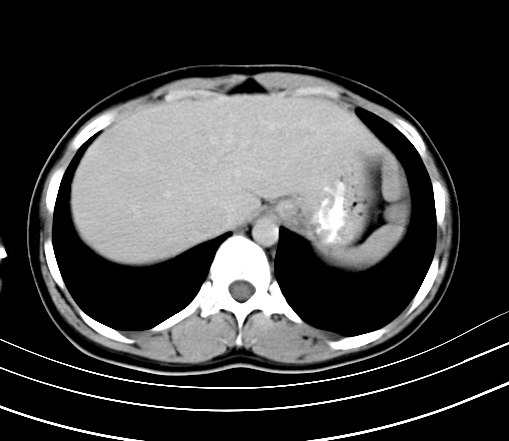

胸部

腹部平扫